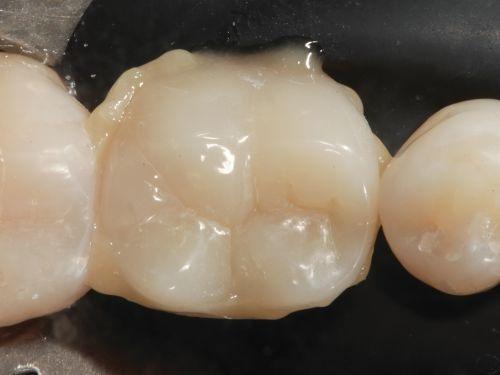

An impression was then taken to obtain a stone model. After the impression was taken, the tooth was temporized, and the patient was dismissed. Once the stone model was set, the model tooth was isolated with a thin layer of wax, and a dentin shade composite resin (GrandioSO 4U Opaque) was applied (Fig. 11). After sculpting the dentin layer, it was photoactivated (Fig. 12). Finally, an enamel shade composite resin (GrandioSO 4U, shade A1) was applied to reproduce the final anatomical contours of the restoration (Fig. 13). The restoration was removed from the model to complete finishing and polishing (Fig. 14).

Fig. 13